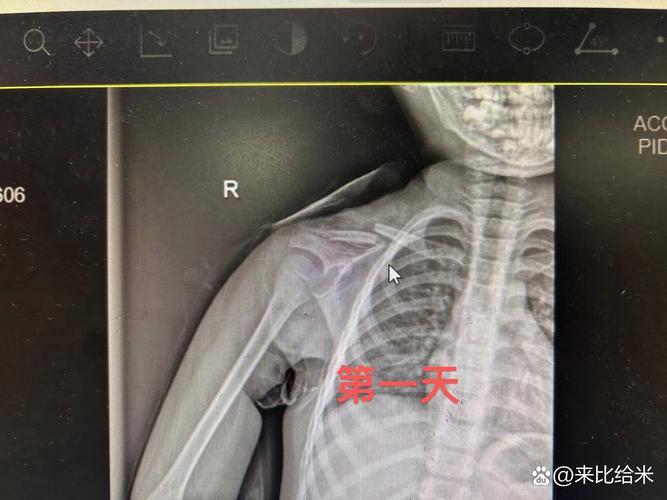

- X光检查(金标准):这是确诊锁骨骨折最直接的方法,通常拍摄胸部正位片,必要时加拍患侧锁骨的斜位或切线位片,X光片可以清晰显示骨折线、骨折类型(完全性/不完全性/青枝骨折)、移位程度等。

X光片特征(描述,非图片):

- 在锁骨骨皮质上可见清晰的透亮线(骨折线)。

- 可能看到骨皮质不连续、错位(移位),断端可能重叠或分离。

- 青枝骨折:骨皮质一侧断裂,另一侧仍连续,像嫩树枝折断一样,常见于儿童。

- 完全性骨折:骨皮质完全断裂,断端可能移位。

- 新生儿锁骨骨折最常见于锁骨中段,且多为横行骨折,移位通常不严重。